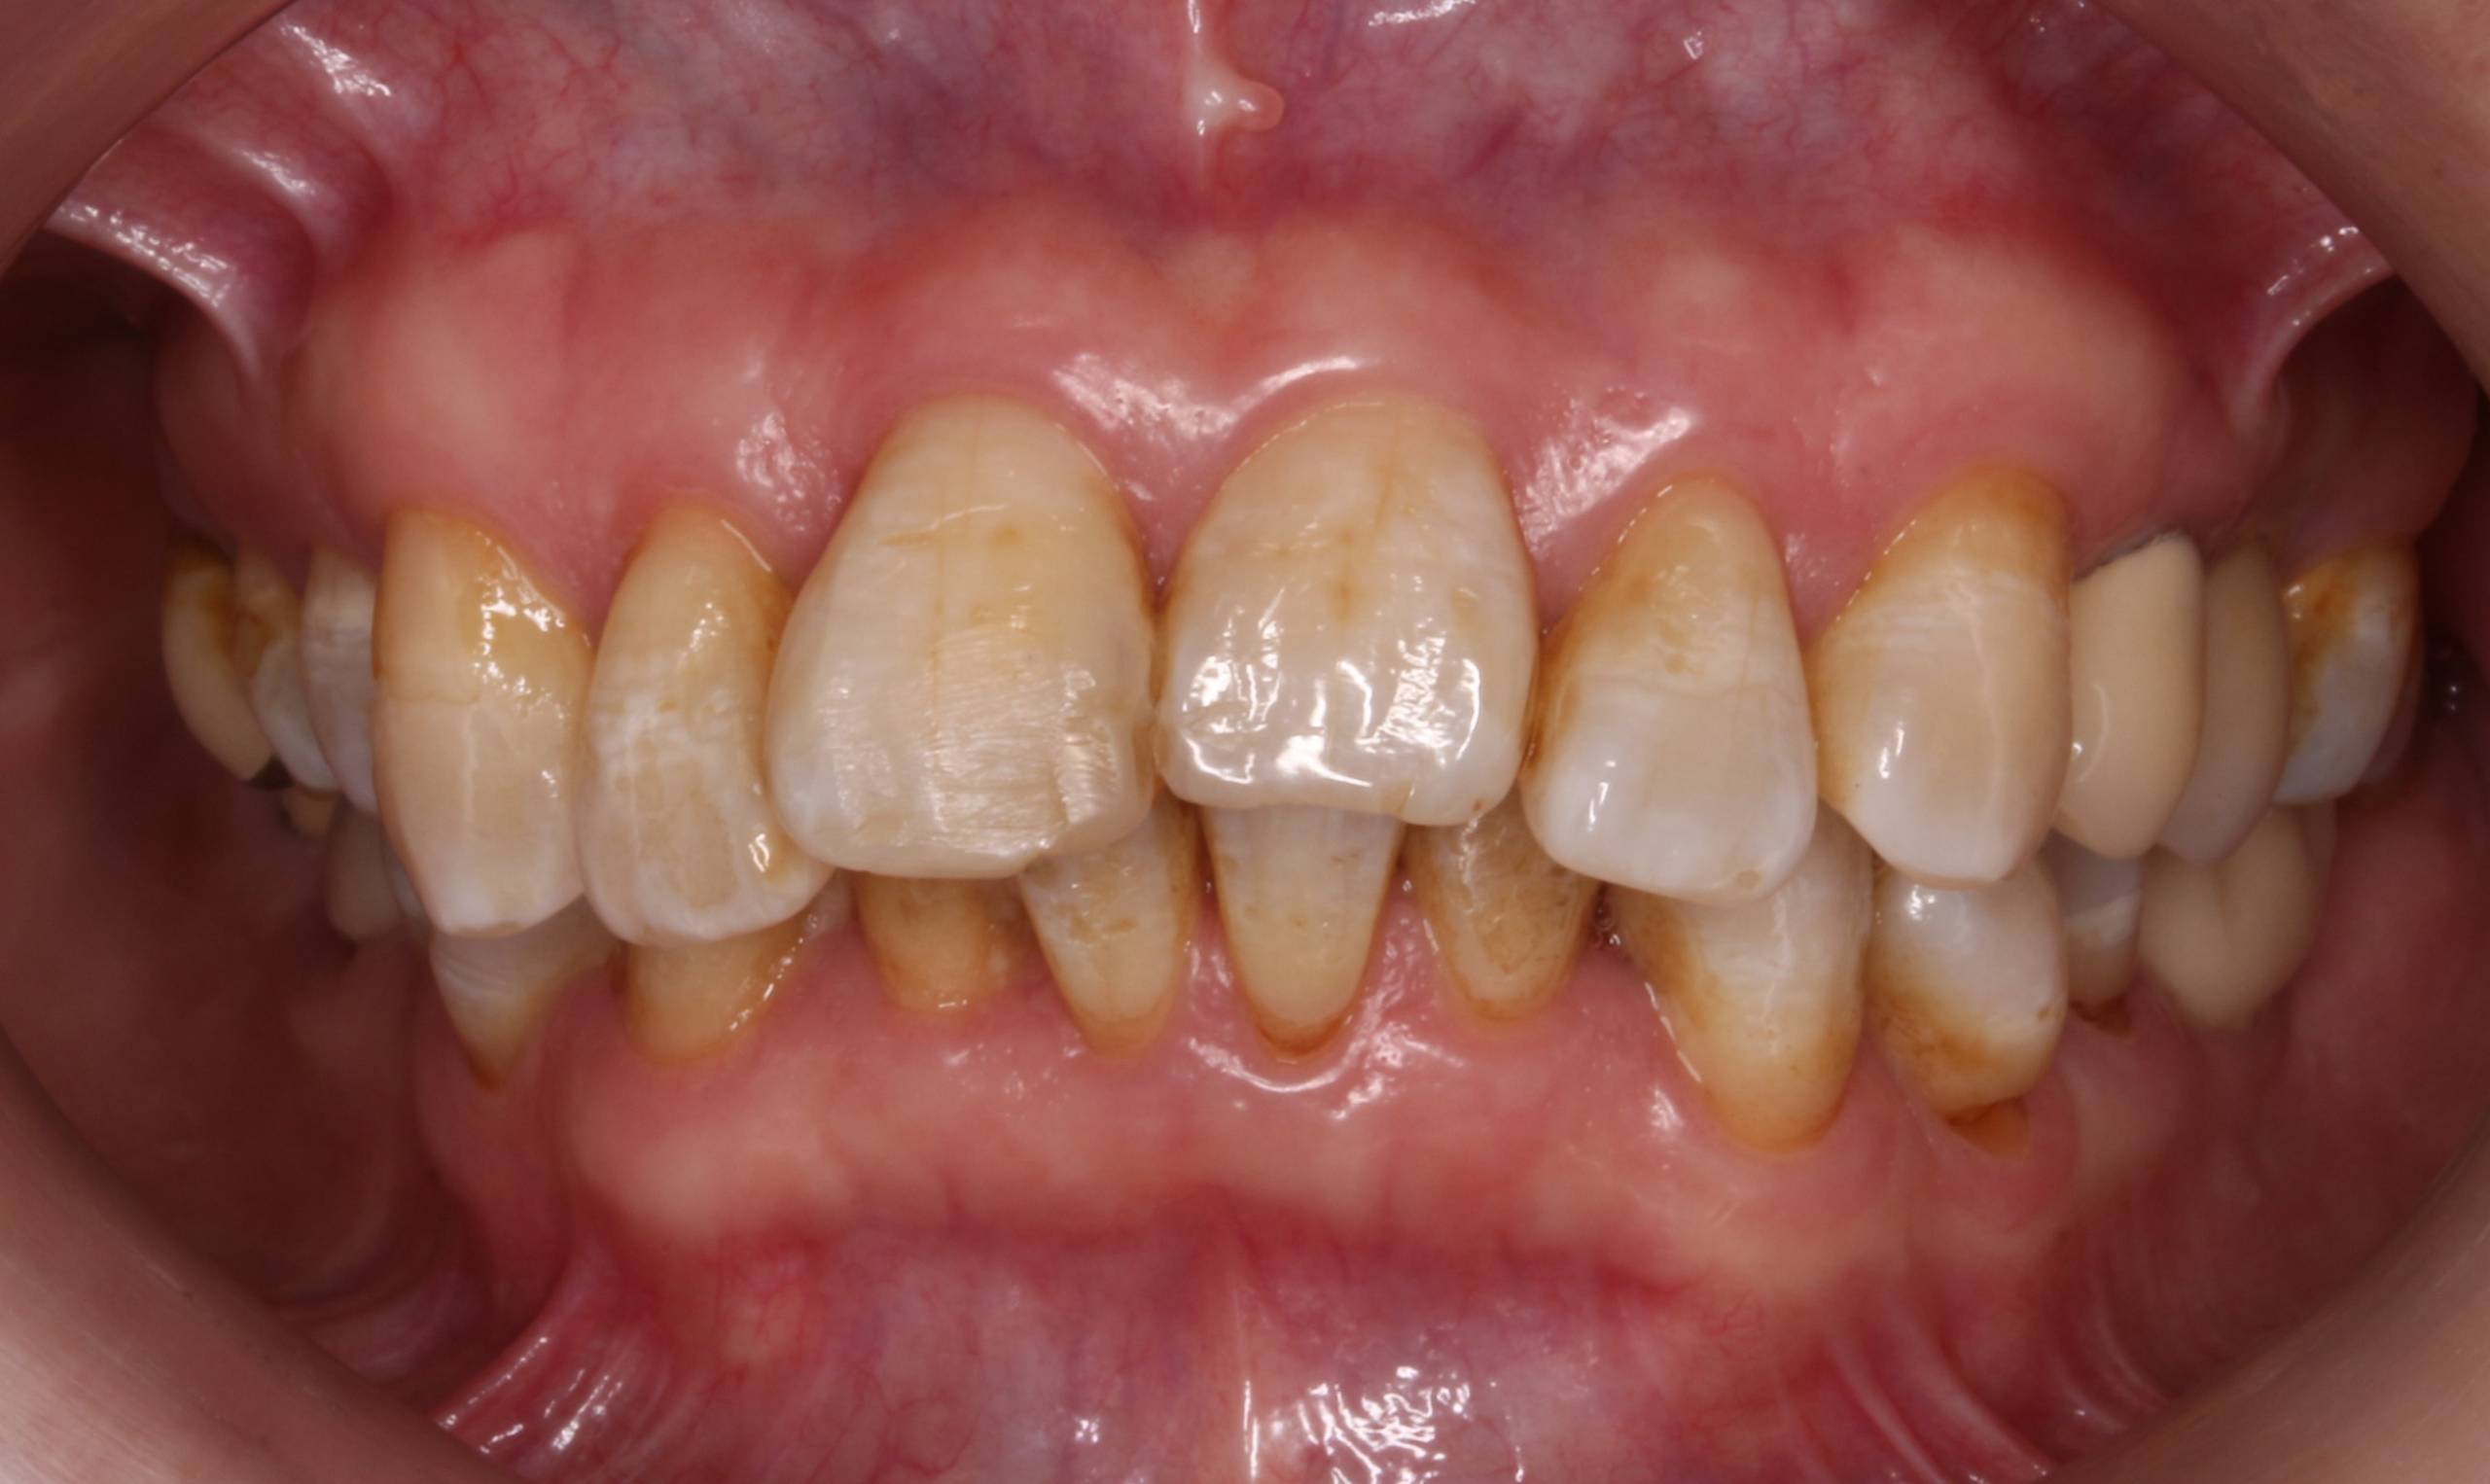

Ortodoncia convencional + Blanqueamiento

Esta paciente de 55 años acudió a nuestra consulta con el objetivo de mejorar su sonrisa. Se le realizó un tratamiento de ortodoncia convencional con brackets metálicos para alinear sus dientes y optimizar su mordida. Posteriormente, completamos el procedimiento con un blanqueamiento dental, logrando reducir notablemente las manchas y realzar el brillo natural de sus dientes. El tratamiento tuvo una duración total de un año y medio, con resultados que transformaron por completo su sonrisa.